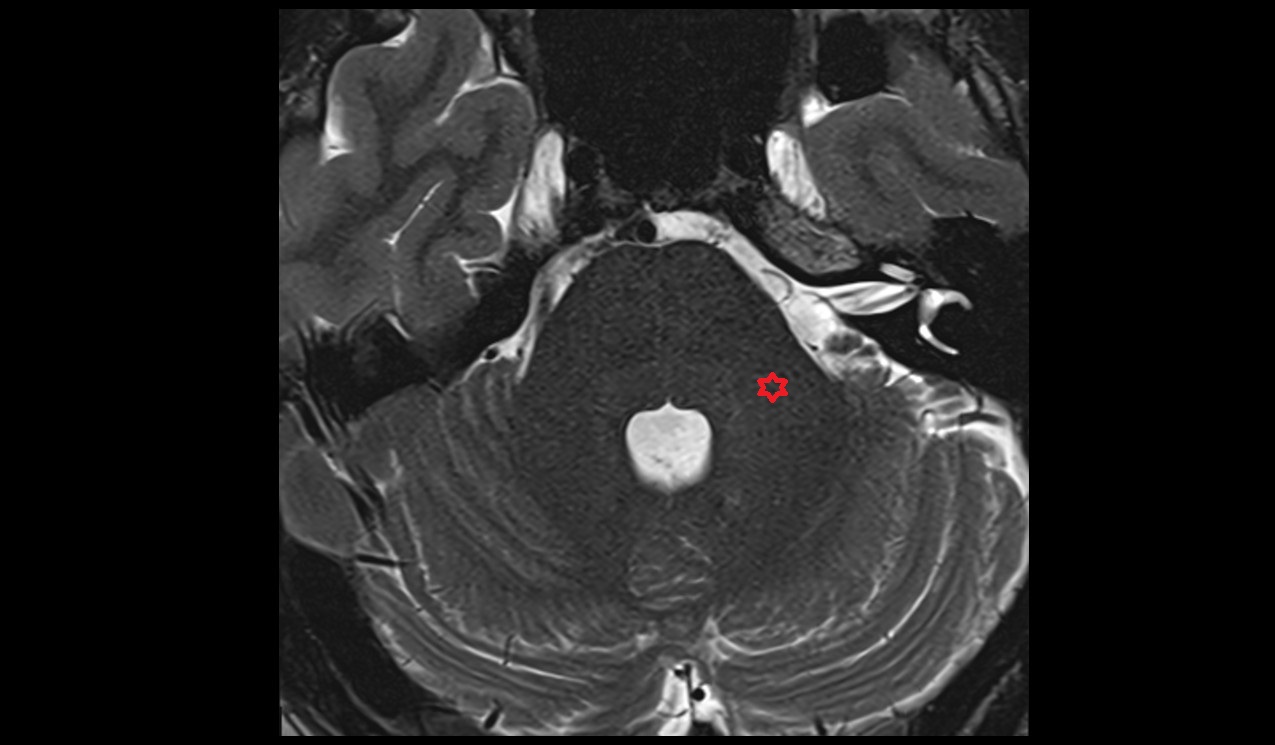

- Peripheral zone of prostate

- Anterior Fibromuscular Stroma of prostate

- Central zone of prostate

- Transitional zone of prostate